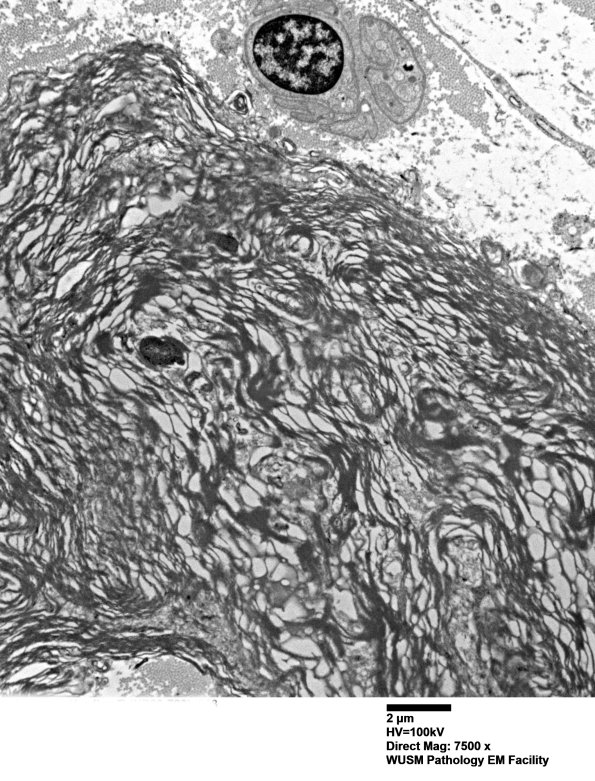

Higher magnification of image #14B1. (electron micrograph)